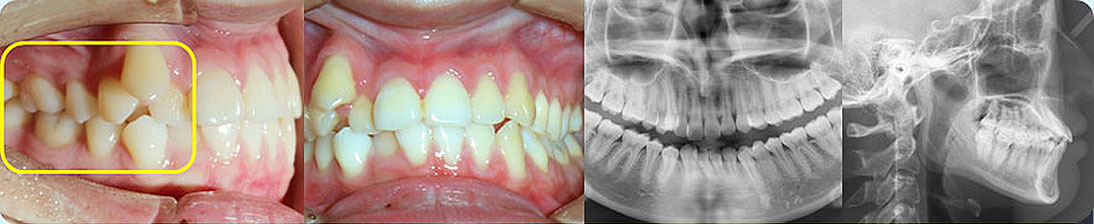

- 【診斷】

先天缺少下切牙2顆

上前牙錯(cuò)位于下前牙后側(cè),前牙無(wú)咬合功能,上牙槽及上唇后縮

打造醫(yī)生:德倫口腔正畸中心鄧毅醫(yī)生

- 【治療方案】

調(diào)整弓形及配合Ⅲ類牽引,實(shí)現(xiàn)頜跳躍

矯治前后對(duì)比

牙列整平排齊,前牙內(nèi)收;覆蓋、覆合正常;尖牙和磨牙達(dá)到中性關(guān)系;上下中線對(duì)齊;下頜后縮改善